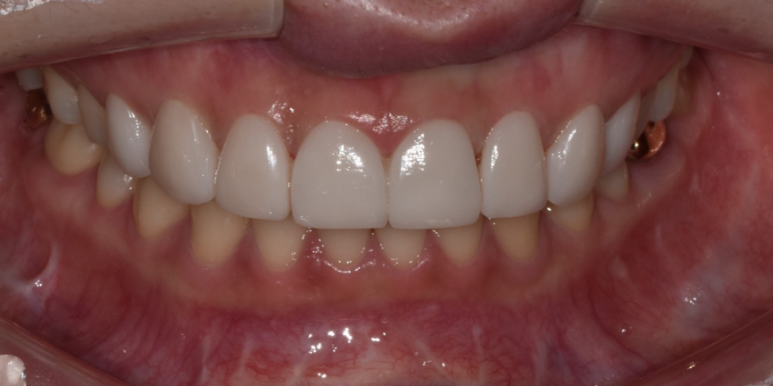

| 교정후라미네이트 치료 사례 4. |

환자분은 교정 후 유지 장치를 착용하고 계신 상태이며,

치아배열은 고르지만 치아 모양과 색상이 마음에 들지 않아 라미네이트 시술을 위해 내원해 주셨습니다.

환자분 역시 삭제량이 많은 것을 원하지 않으셨기에 대문니 끝 파절된 부분과 보철물 부착을 위한 최소삭제로 진행을 도와드렸습니다.

(전) 2022-08-02, (후) 2022-08-11

평소 이갈이가 있다고 하셔서 이갈이 장치 제작 및 사용을 권장해 드렸는데요.

지속적인 이갈이로 보철물에 힘이 가해지면, 라미네이트가 깨질 우려가 있기 때문입니다.

따라서 평소 이갈이를 하시는 분들은 시술 전 담당 주치의에게 미리 말씀하시고, 장치를 제작하여 착용하시는 것이 좋습니다.